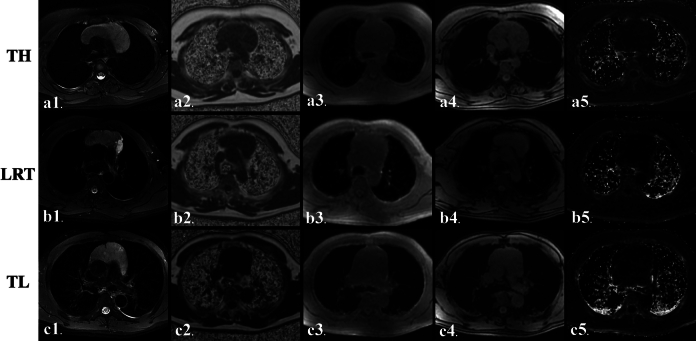

Objectives: Detection of fat content in thymic lesions is essential to differentiate thymic hyperplasia from thymic tumors. This study assesses the reliability and efficacy of "iterative decomposition of water and fat with echo asymmetry and least-squares estimation quantization" IDEAL-IQ magnetic resonance sequence in distinguishing thymic hyperplasia from low-risk thymoma and thymic lymphoma in adulthood.

Methods: Thirty patients with thymic hyperplasia, 28 low-risk thymomas, and 13 thymic lymphomas were respectively enrolled. All subjects underwent conventional thorax magnetic resonance imaging and IDEAL-IQ sequence. The fat fraction (FF mean and FF total ), signal intensity index, and R2* values of the lesions were compared for differences among 3 groups by the Mann-Whitney U and Kruskal-Wallis tests. Receiver operating characteristic curve analysis was performed to determine the differentiating efficacy.

Results: Both FF mean and FF total values in patients with thymic hyperplasia are significantly higher than those in patients with low-risk thymoma and thymic lymphoma (FF mean : 26.41% vs 1.78% and 1.93%, FF total : 27.67% vs 2.21% and 2.44%; both P  < 0.001), whereas there was no significant difference in these values between low-risk thymomas and thymic lymphomas (both P  > 0.05). Similarly, signal intensity index and R2* values of thymic hyperplasia were significantly higher than those of patients with low-risk thymoma and thymic lymphoma ( P  < 0.001). Receiver operating characteristic curve analysis showed that FF mean had an area under the curve of 0.998, with a cutoff of 4.78% yielding 95.12% sensitivity and 100% specificity, and FF total had an area under the curve of 0.994, with a cutoff of 8.57% yielding 97.56% sensitivity and 96.67% specificity in distinguishing thymic hyperplasia from tumors.

Conclusions: IDEAL-IQ sequence provides accurate fat quantitative parameters and can differentiate thymic hyperplasia from thymic neoplasms with robust efficacy and reliability.